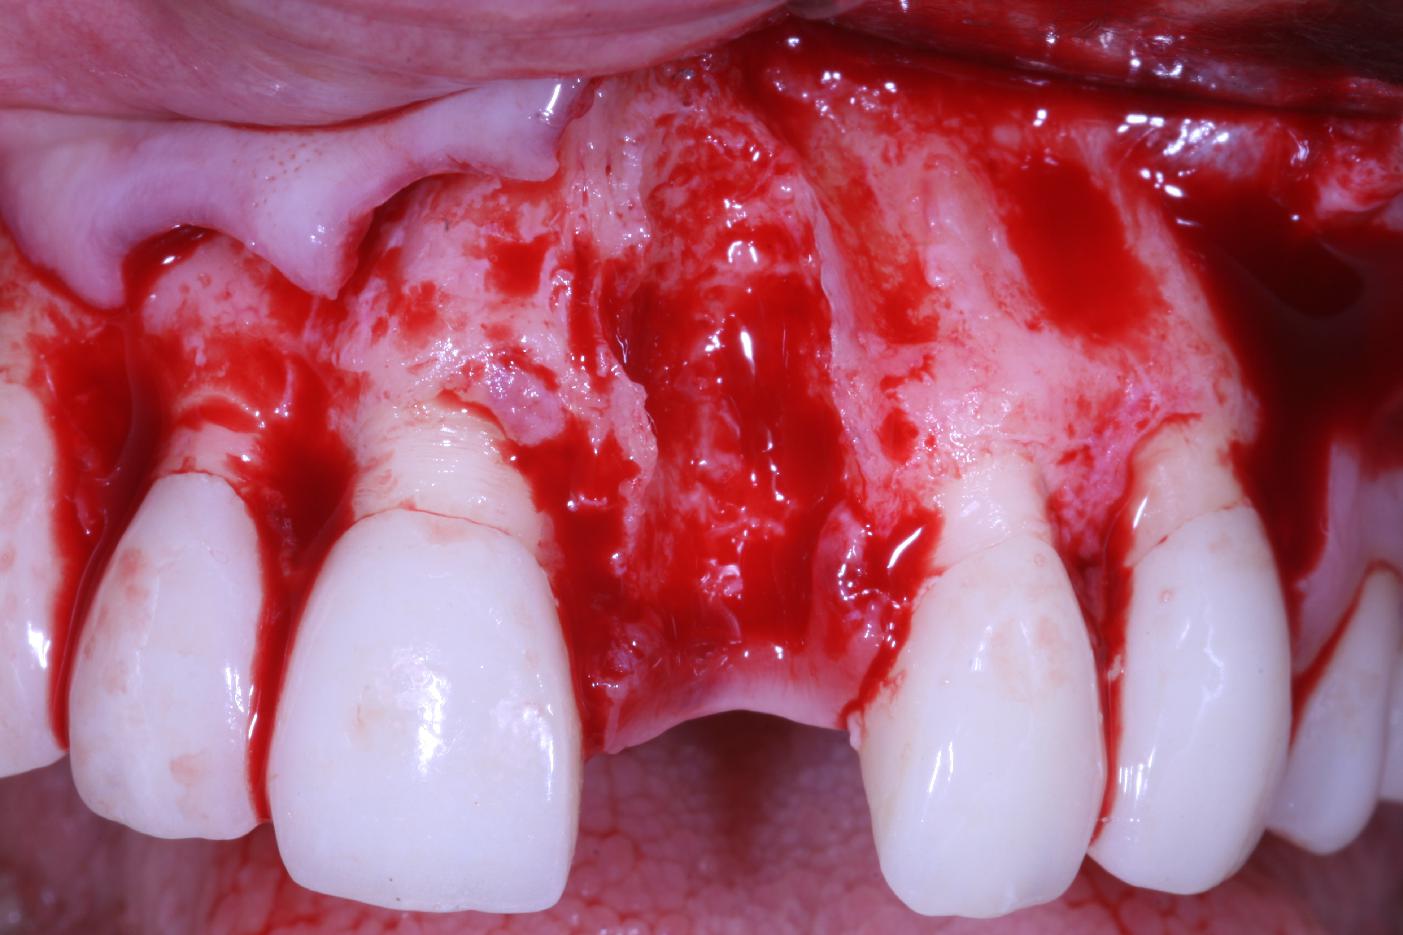

Augmentation of a traumatic soft tissue defect-Rathe

Initial clinical situation with traumatic loss of tooth 21